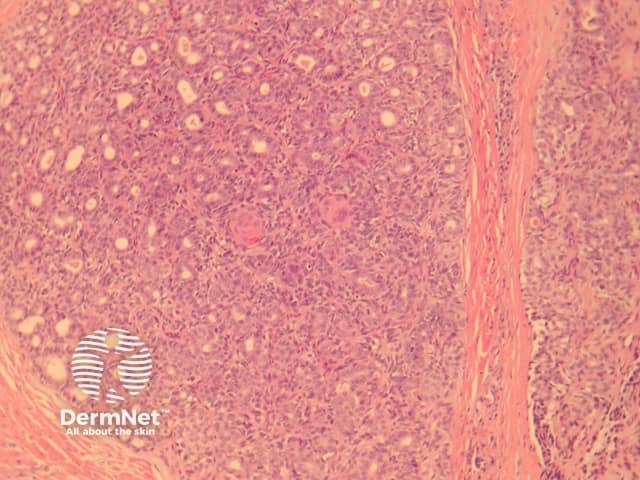

In aggressive digital papillary adenocarcinoma, sections show a dermally based tumour, which may connect with the overlying epidermis (figure 1). The tumour may be cystic, papillary, ductal or solid. The example illustrated here has a predominantly solid and ductal morphology with only focal areas of papillary formation. The cells are basaloid, show enlarged atypical nuclei, large nucleoli and increased mitoses (figures 1-6). Squamous metaplasia within the tumour may be seen (figure 5).

Figure 1